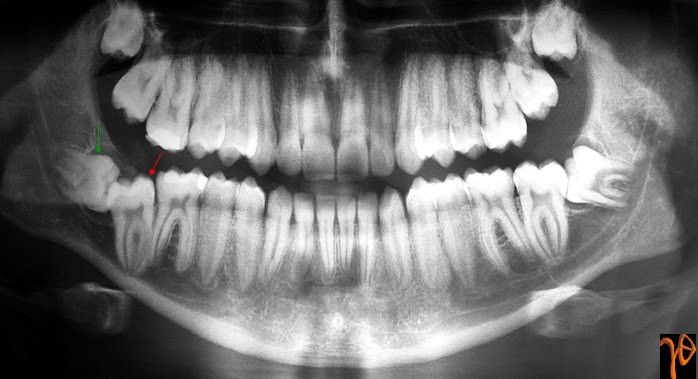

Οι πιο συχνές βλάβες στο στόμα είναι τα αποστήματα, τα οποία όταν οφείλονται σε μικροβιακές λοιμώξεις δοντιών της άνω γνάθου μπορούν να εκδηλώνονται και στην υπερώα (Εικόνα 3). Η θεραπεία τους προϋποθέτει την θεραπεία του υπεύθυνου δοντιού.

Εικόνα 3. α. Απόστημα που οφείλεται σε γομφίο οδόντα (βέλος), β. Απόστημα που οφείλεται σε τομέα οδόντα (βέλος).